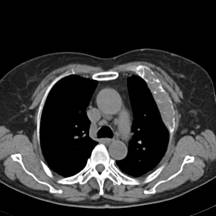

典型病例1:患者鞠xx,女,68岁,住院号:488141,因左胸痛1月余入院。2015年3月31日胸部增强CT示:左肺下叶2.5cmx2.8cm占位,左侧第三前肋骨溶骨性转移、形成厚约3cm肿块,左侧腋窝淋巴结2.1cmx4.1cm及前纵膈淋巴结转移。患者于2015年4月1日经CT引导下穿刺活检、病理证实为左肺下叶腺癌。于2015年4月5日对其采用125I放射性粒子置入治疗。治疗3个月随访,患者胸痛缓解,左肺下叶原发病灶消失,粒子聚集;左侧第三前肋骨基本恢复正常形态;前纵膈淋巴结消失,粒子聚集;左侧腋窝淋巴结缩小2/3。目前患者生活质量良好,可从事一般家务劳动。

术后三个月CT片: